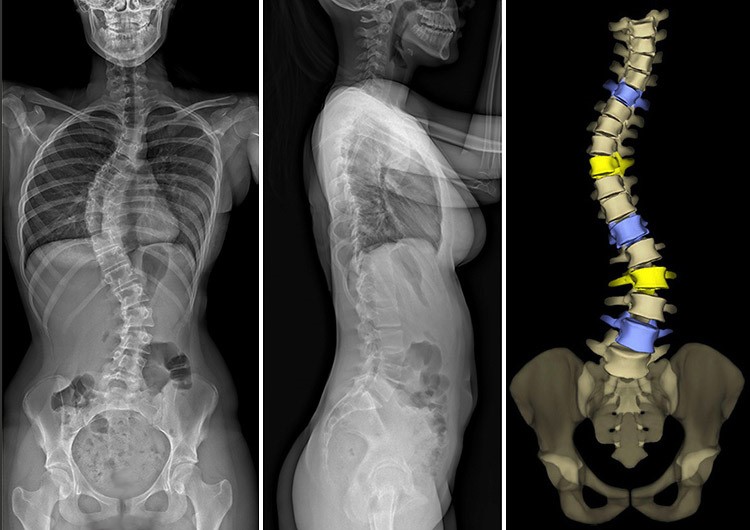

EOS(全身骨骼三維建模成像系統)以低輻射劑量對患者全身肌肉骨骼進行正側位同步掃描,在獲得患者正側位雙平面全身1:1的X射線影像基礎上,通過三維建模工作站對患者全身骨骼進行三維重建,從而測量AVR角,本研究以此為金標準對比三維超聲。

EOS

(圖片源於網絡)

每位患者EOS三維建模加AVR測量平均花費20分鐘,三維超聲掃描成像及角度測量平均花費3分鐘。